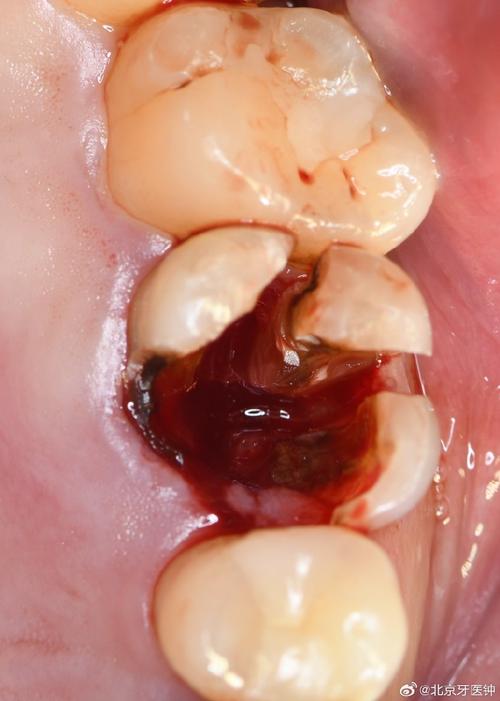

(图片来源网络,侵删)- 这通常指的是牙齿排列不齐,可能是拥挤、扭转、前突(龅牙)、反颌(地包天)、深覆颌等错颌畸形。